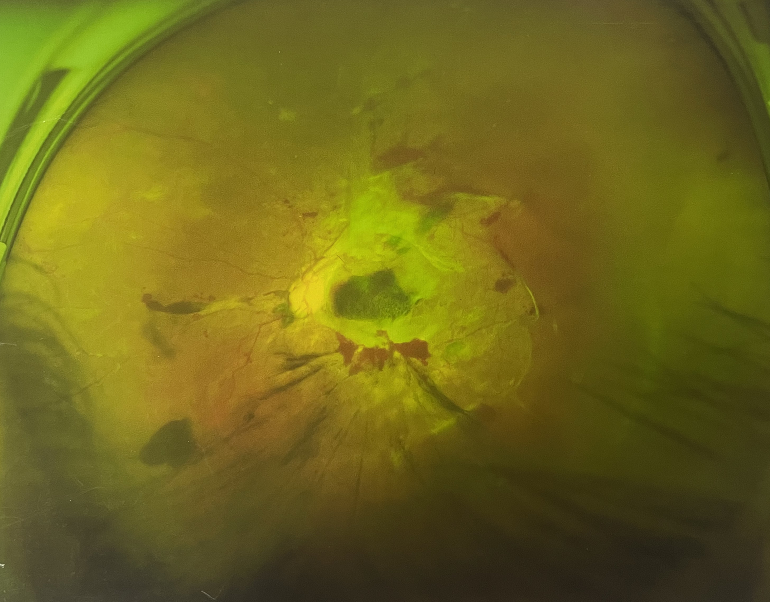

由于王女士的左眼沒有聽從醫(yī)生盡快做手術(shù)的建議,一直耽誤,從4月前的0.4視力逐漸下降到僅剩眼前手動(dòng),導(dǎo)致左眼發(fā)展到糖尿病視網(wǎng)膜病變VI期(屬于6期糖網(wǎng)中的晚期),已經(jīng)產(chǎn)生大量新生血管+纖維增值+廣泛牽拉性視網(wǎng)膜脫離,由于耽誤了病情,且病情發(fā)展異常迅速,導(dǎo)致目前左眼連保住眼球都很困難。

“而如果4月余前,左眼及時(shí)手術(shù)(當(dāng)時(shí)左眼病情比右眼輕,增殖膜還未累及黃斑),左眼將恢復(fù)的比右眼還好,甚至可以恢復(fù)到0.8或1.0,而現(xiàn)在連保住眼球的機(jī)會(huì)都很渺茫”,張小虎醫(yī)生表示實(shí)在可惜。

4個(gè)月前的左眼

左眼發(fā)展到糖尿病視網(wǎng)膜病變VI期